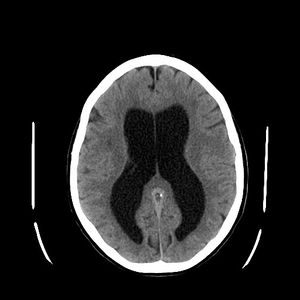

استسقاء المخ كما يظهر في الأشعة المقطعية على المخ. المناطق السوداء في منتصف المخ هي تضخم غير طبيعي ومملوء بالسوائل. | |

- الأشعة المقطعية : وتعطي صور واضحة عن الحالة ومكان الانسداد.